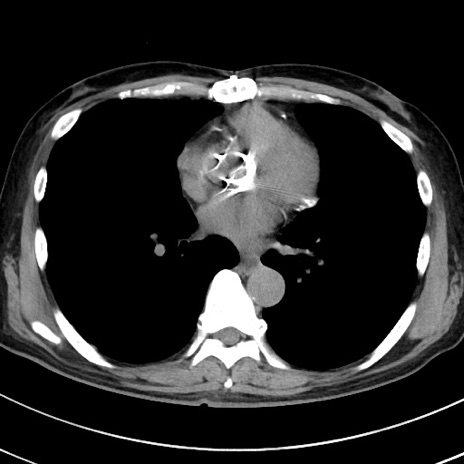

症例38(横断像)

【症例】70歳代 男性

【主訴】腹痛・嘔吐

【現病歴】昨晩より、嘔吐・腹痛あり。今朝になっても嘔吐あり。来院。

【既往歴】心臓バイパス手術、開腹胆摘、腸閉塞

【身体所見】BP 107/71mmHg、HR 116/min、腹部:平坦、軟、下腹部に軽度圧痛あり。反跳痛なし。

【データ】WBC 15100、CRP 0.32